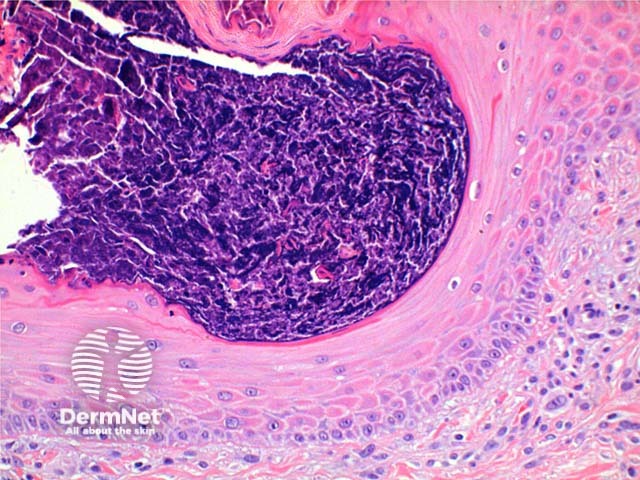

The low power view of perforating collagenosis shows an invaginating epidermal process (Figure 1). There is hyperkeratosis overlying a cup shaped depression or invagination in the epidermis. There is prominent epidermal hyperplasia, which encompasses a central basophilic plug of keratin, collagen and inflammatory debris (Figure 2). On careful sectioning, this is continuous with altered collagen in the underlying dermis, which is being expelled by the process of transepidermal elimination. Within the epidermal plug bright eosinophilic altered collagen fibres can be seen (Figures 3 and 4).

Figure 3